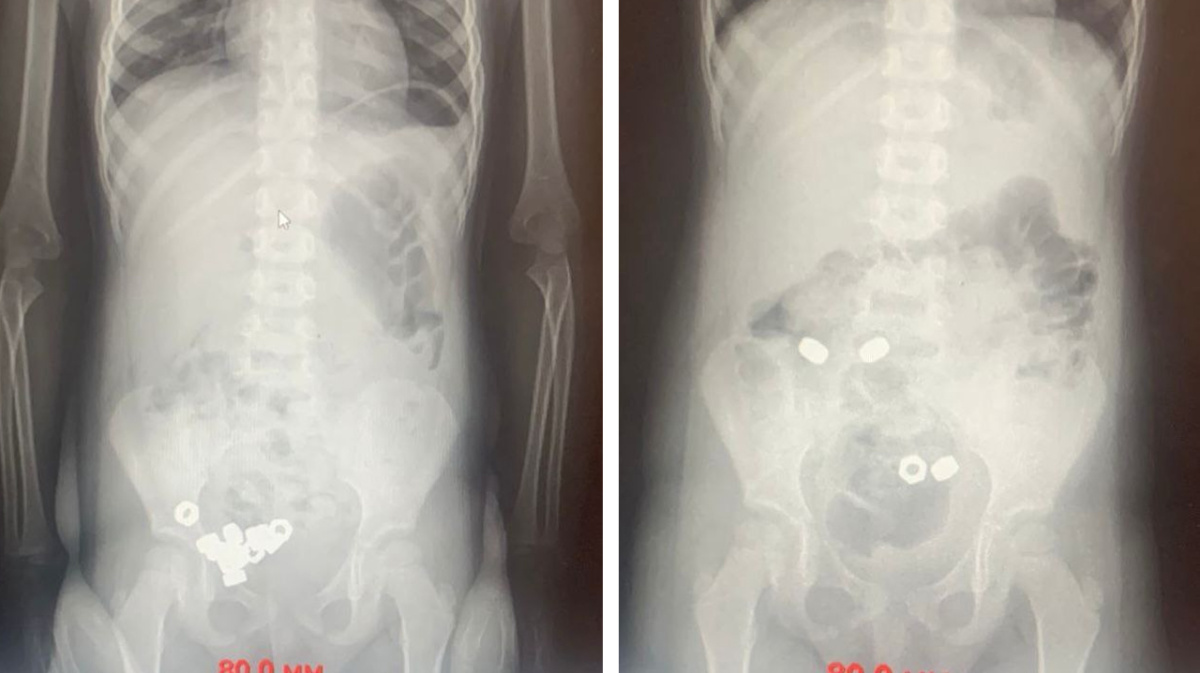

Ребенок проглотил или нет

Ребенок проглотил или нет 103 фотографий